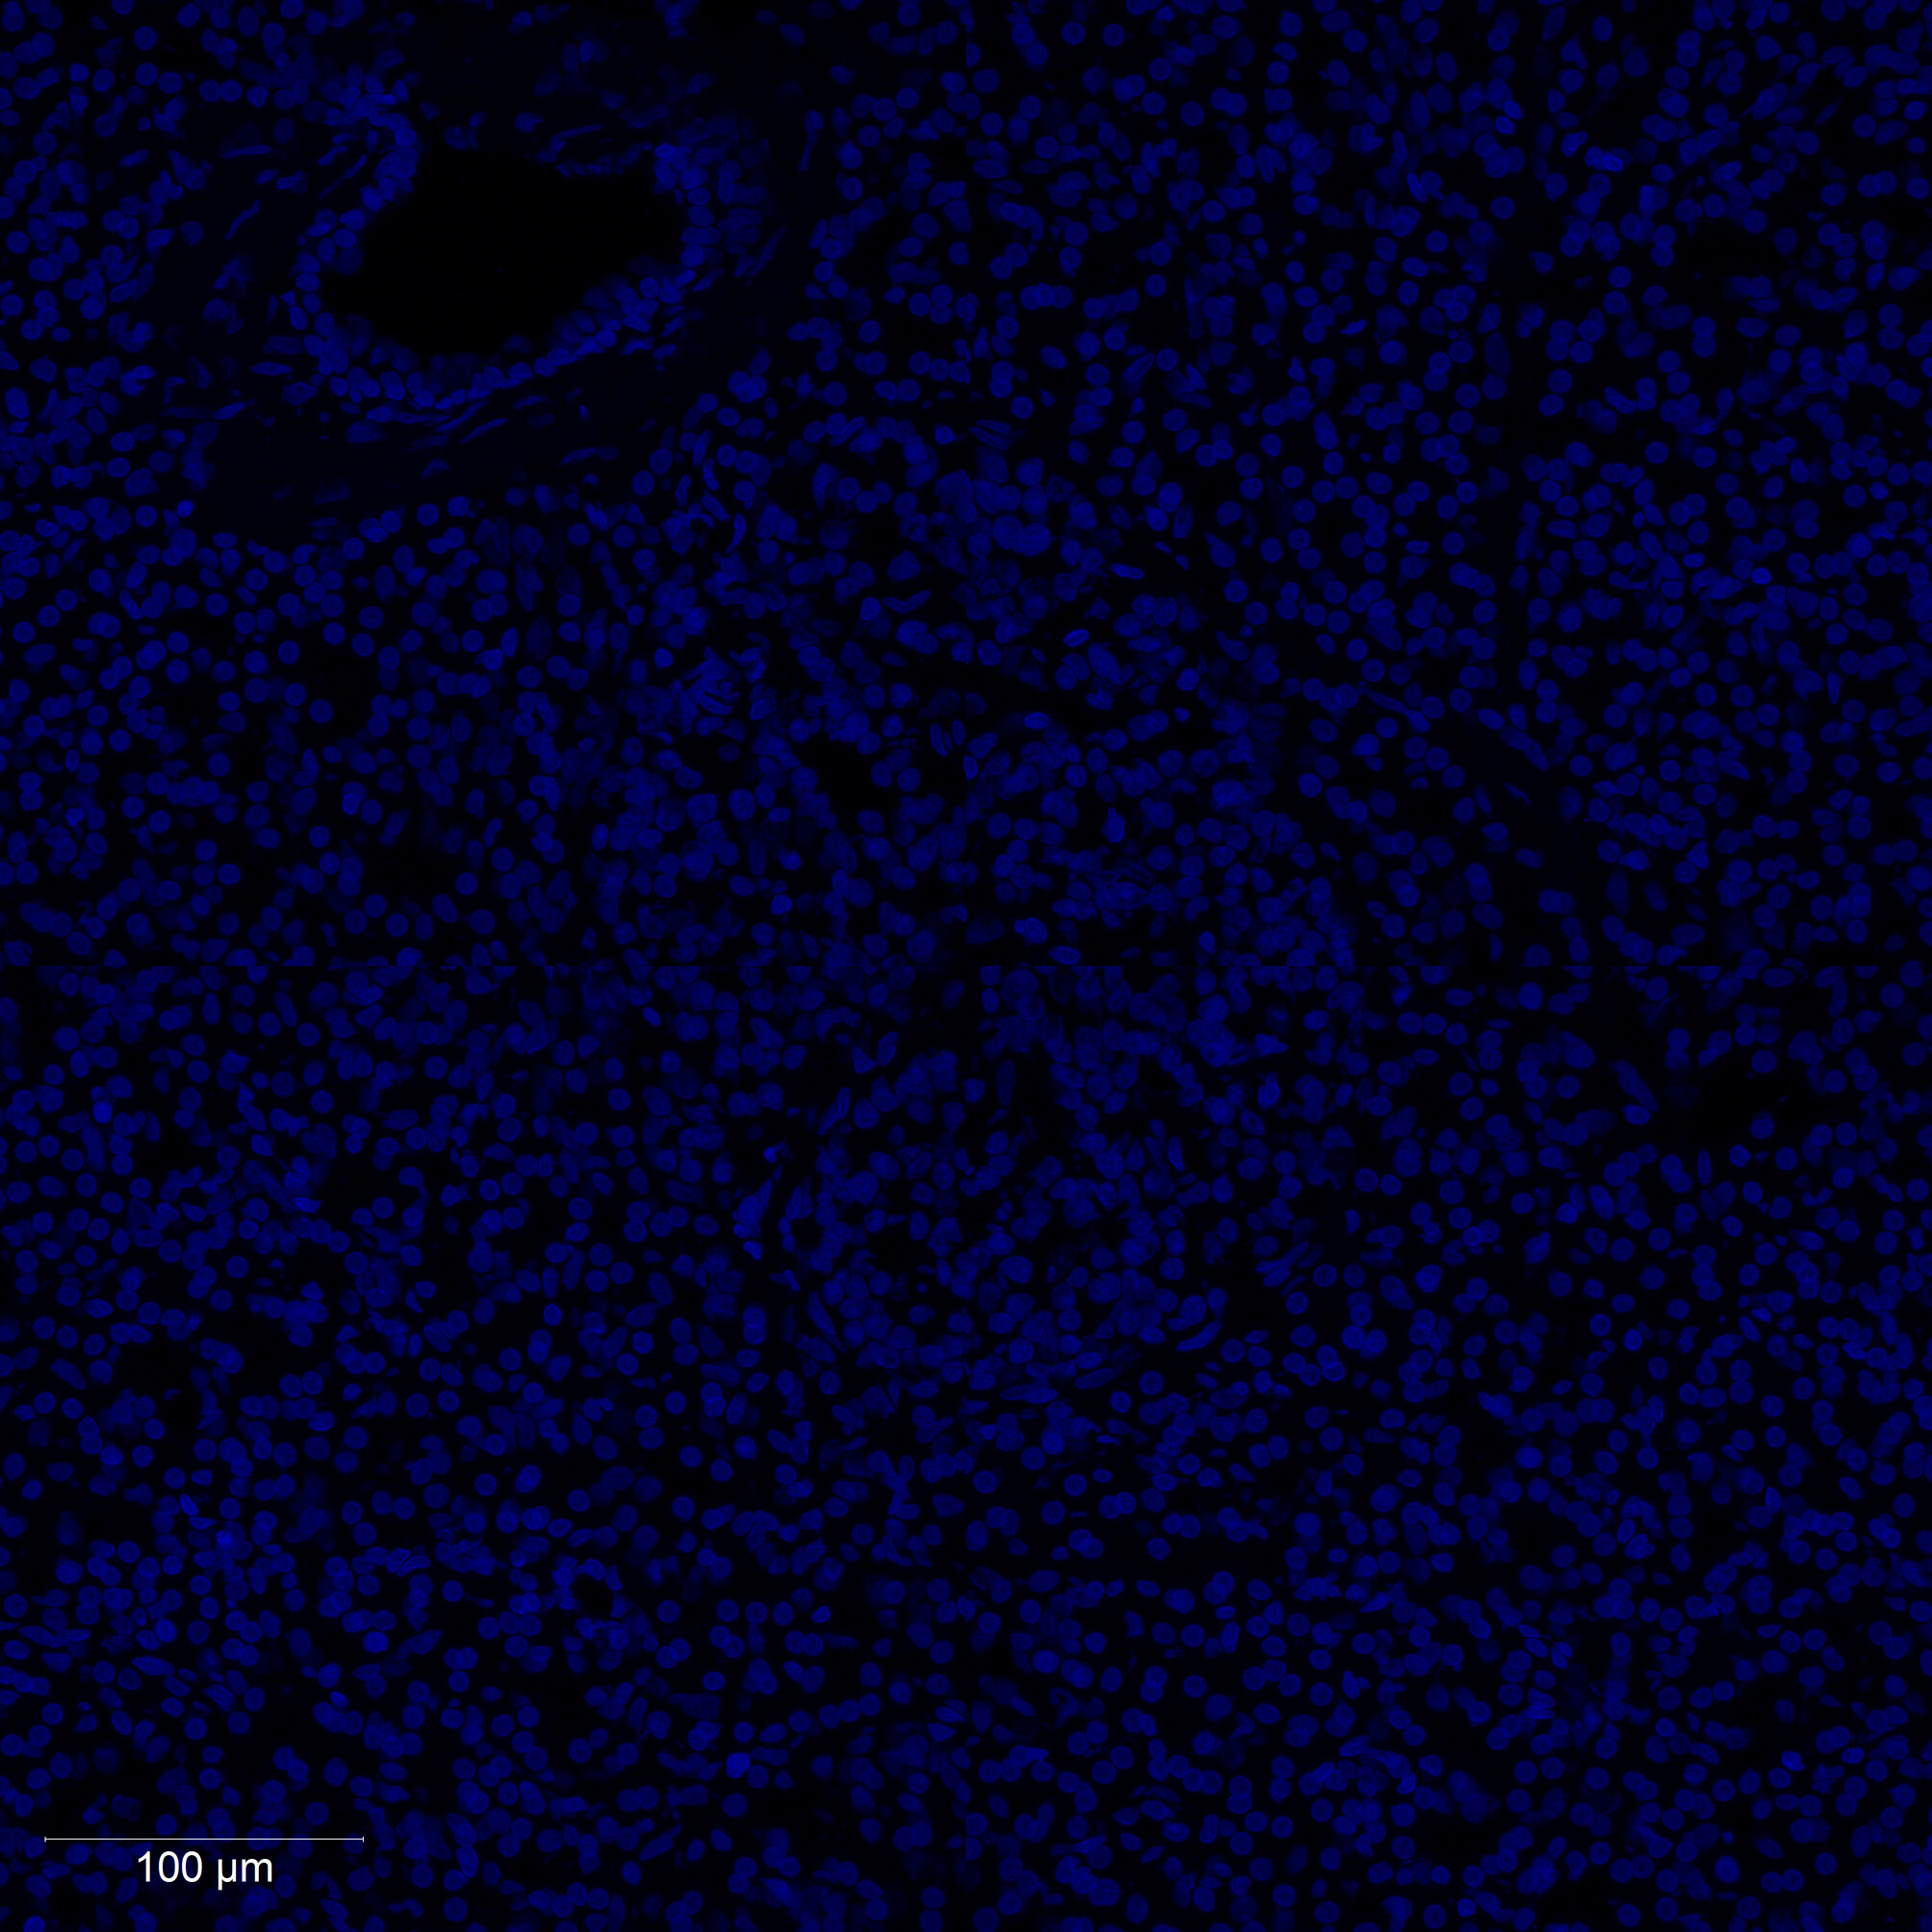

Human pancreatic tissue sections were imaged with multiplex immunofluorescence using DAPI (nuclear), INS (insulin/beta cells), and GCG (glucagon/alpha cells) channels at 10X magnification.

Nuclear boundaries were detected using CellPose 2.0 deep learning segmentation on the DAPI channel. Cell boundaries were refined and ROIs extracted in FIJI/ImageJ using custom macros.